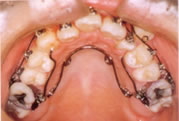

○クウォードへリックス・リンガルアーチ

主に内側から歯を押して必要なスペースを作ります。太いワイヤーの弾力で歯を動かす力を発揮します。